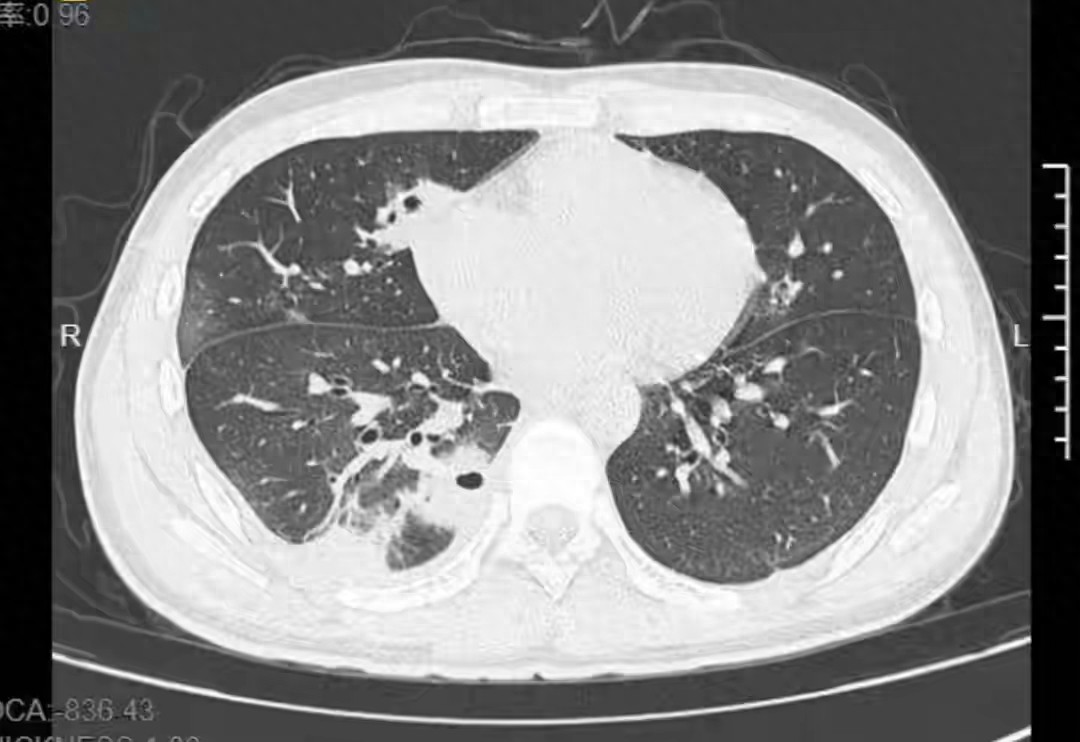

近日,浙江宁波。20岁大学生小林备考熬夜后,面部出现一颗红肿的痘痘,没洗手便直接挤压。几天后,痘痘未见好转,反而出现发烧、咳嗽、咳痰及右下胸针刺样疼痛症状。CT检查后发现,小林的肺部竟然出现了十多个空洞,肺组织部分坏死,被确诊为血源性肺脓肿,经过12天的抗生素治疗,才康复出院。

小林的故事,或许在很多人眼里,只是个意外,但它背后隐藏的风险,却在提醒我们:健康的“隐形危机”正潜伏在生活的每一个角落。那颗红肿的痘痘,或许只是一个微不足道的小问题,但挤压它的瞬间,却打开了一扇通往“未知”的大门——肺部空洞、坏死、甚至生命垂危。